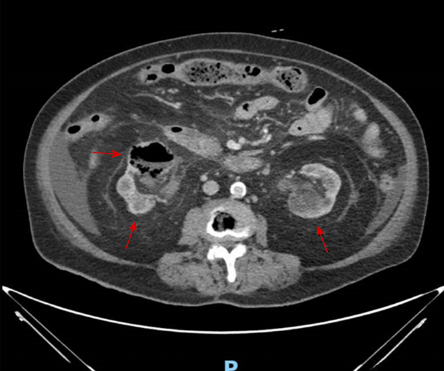

The patient was a 71-year-old Chinese woman, with a history of poorly controlled DM on insulin therapy, and end-stage renal failure (ESRF) managed by peritoneal dialysis (PD). She presented with a two-day history of gross hematuria, dysuria, and fever, without abdominal/flank pain. On examination, she was hemodynamically stable and afebrile, with a soft and non-tender abdomen and negative bilateral renal angle tenderness. Initial laboratory tests revealed leukocytosis and elevated C-reactive protein. Urinalysis demonstrated significant pyuria and hematuria, and urine culture grew Klebsiella sp. Blood and PD fluid cultures were negative for pathogens [Table 1]. Computed tomography scan of the abdomen and pelvis revealed bilateral renal abscesses with gas locules within the right renal parenchyma and pelvicalyceal system [Figure 1], consistent with Huang and Tseng class II emphysematous pyelonephritis.6

Figure 1: Contrast-enhanced CT image of the abdomen and pelvis showing bilateral renal abscesses (red arrows) and right-sided emphysematous pyelonephritis. Dashed arrow indicates the location of gas within the right renal pelvicalyceal system.